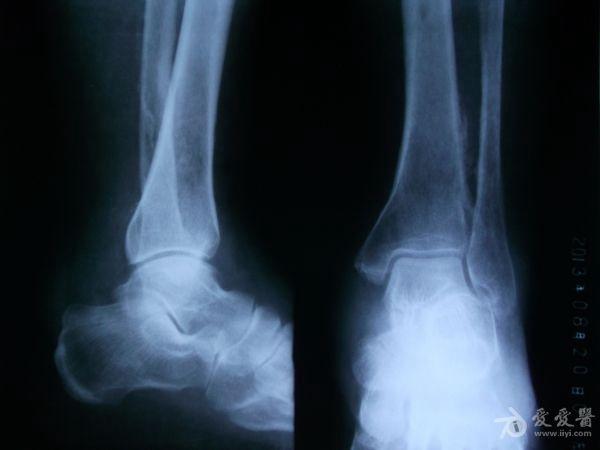

男性,56岁,左小腿静脉曲张十多年了吧,好像做过手术。现在他的整条左小腿肿胀,皮肤发黑,靠近外踝的皮肤出现溃疡。片子不太清楚,因为是基层,条件艰苦没CR。请各位前辈指点下,该患者的左胫、腓骨是什么状况,应该怎样发报告?谢谢!

患者有静脉曲张的病史,现在小腿的肌肉和皮肤都出现缺血坏死的症状;而胫腓骨X光片示胫腓骨下段向对面骨皮质增生模糊,有明显的骨膜反应;也还是考虑骨质长期缺血缺氧所致,类似肺癌所致骨皮质增生的改变。当然,骨髓炎和骨肉瘤等来源骨质本身的疾病不能完全排除。

胫腓骨下段骨皮质模糊,出现葱皮样骨膜反应,骨髓腔稍狭窄,软组织情况不清。考虑急性骨髓炎可能,为排除骨肉瘤,建议CT。